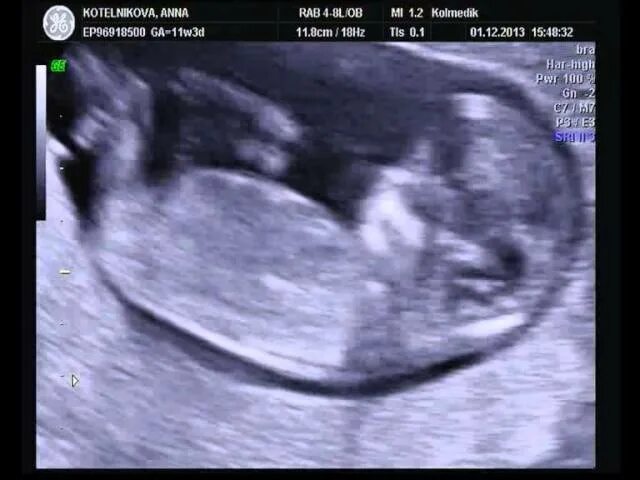

Ему было 11 недель